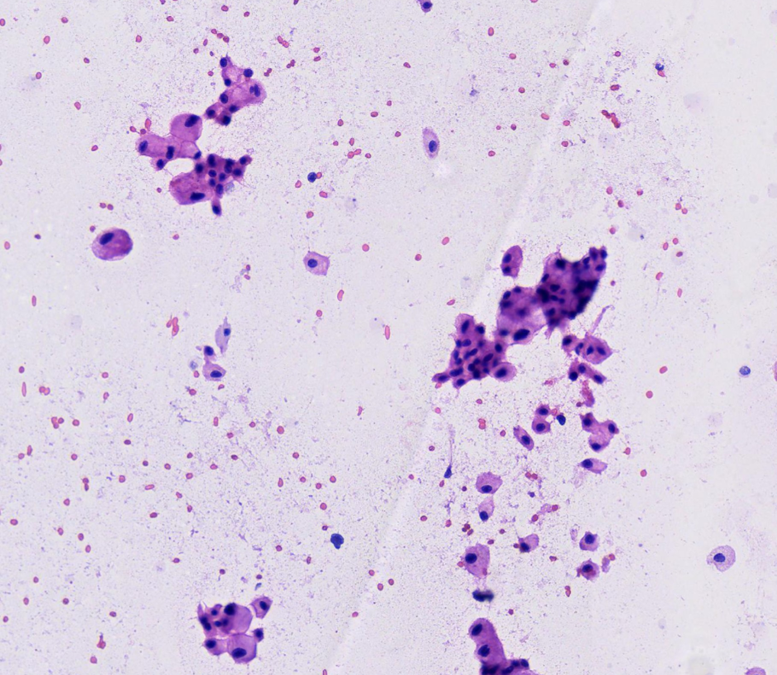

Paciente mujer de 43 años, G0-P000 con antecedentes de hipertensión arterial en tratamiento e historia familiar de cáncer (carcinoma de células de Merkel). Acude por presentar dolor punzante en flanco izquierdo de una semana de evolución. Al examen físico, se palpa masa abdominal móvil y dolorosa. La TC abdominal revela masa sólida ovoidea, de bordes definidos y aspecto encapsulado que mide 139 x 105 mm, asociada a áreas quísticas (Fig 1). Ante estos hallazgos, se realiza nefrectomía radical izquierda. Con la intención de tomar decisiones clínicas inmediatas, se realiza impronta del tumor renal en pieza operatoria observándose células tumorales poligonales con abundante citoplasma eosinofílico granular, membrana citoplasmática bien definida y bordes celulares acentuados. El resultado fue neoplasia de tipo oncocítica que favorece carcinoma cromófobo (Fig 2-5), confirmado histológicamente (Fig 6). Paciente evoluciona favorablemente.

El carcinoma cromófobo de células renales presenta rasgos citológicos característicos, como células poligonales con citoplasma abundante eosinofílico o reticular y membranas celulares bien definidas. Sin embargo, hallazgos clásicos como los halos perinucleares y núcleos arrugados pueden no ser tan evidentes, como en nuestro caso, generando solapamiento con el oncocitoma, principal diagnostico diferencial, que muestra mayor monotonía celular y citoplasma homogéneo, sin reticulación ni vacuolización.3

En la impronta citológica, los bordes bien delimitados permitieron orientar nuestro diagnóstico hacia un carcinoma cromófobo. Esta técnica constituye una herramienta diagnóstica útil en el intraoperatorio para toma de decisiones rápidas contribuyendo así a una adecuada planificación quirúrgica y manejo terapéutico del paciente.